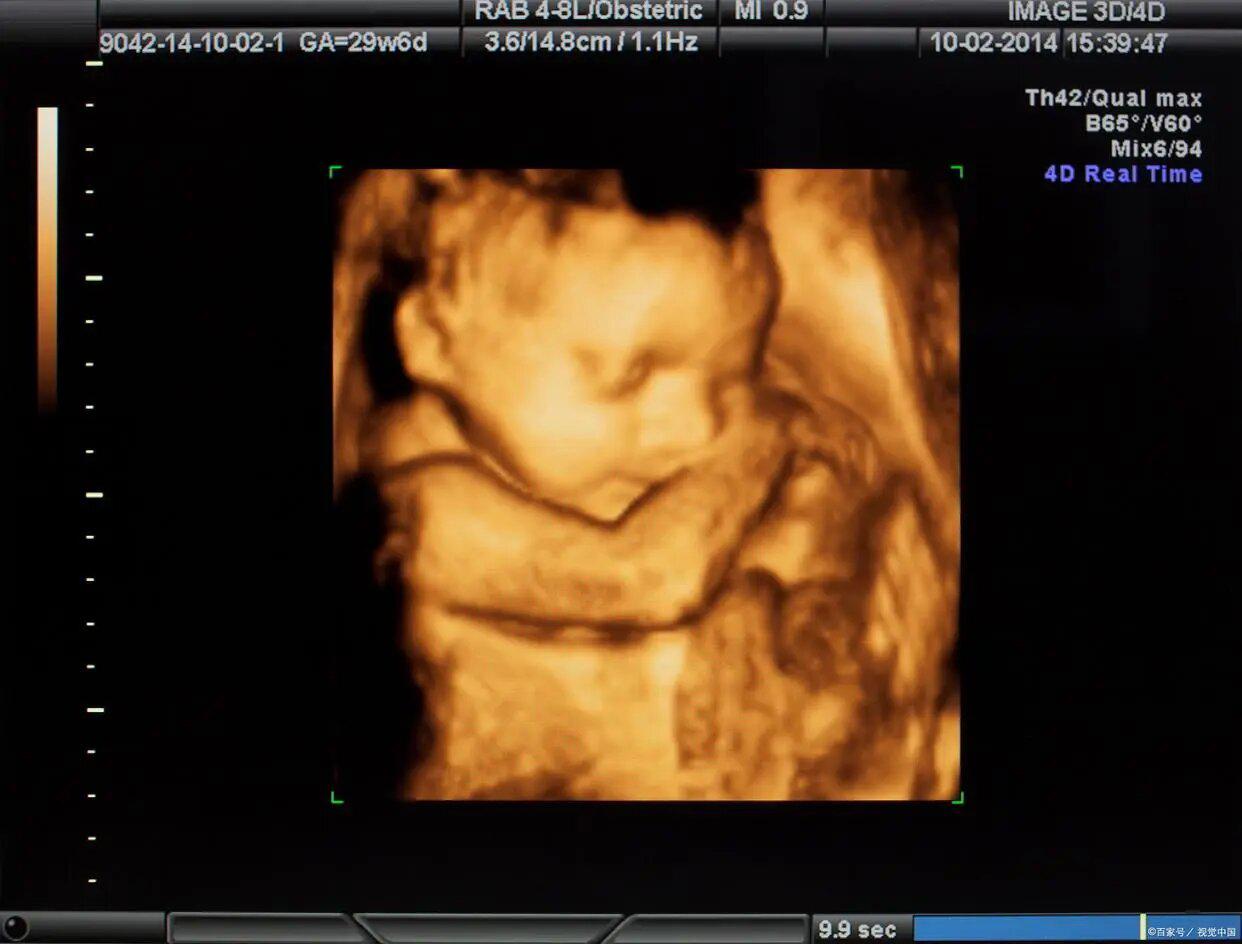

四维彩超是指利用高频声波在人体内部产生的回波图像进行图像诊断的技术。与传统的二维彩超相比,四维彩超能够提供更加详细、立体和实时的图像信息。它可以显示胎儿的脸部、四肢、心脏等器官,并能观察其活动,甚至可以实时观察到胎儿的表情变化。这对于孕妇来说,将会是一次难以忘怀的体验。

在过去的几年里,四维彩超已经成为了孕妇及家庭的常规选择。四维彩超不仅能够提供胎儿的各项生物参数,如胎儿的位置、胎心率、体重等,还能够观察到一些异常情况,如畸形、染色体异常等。这为医生提供了更多的信息,以便于更准确地进行诊断和判断。同时,四维彩超也为孕妇家庭提供了更多的机会去了解和与胎儿进行亲密接触,增强了亲子情感。